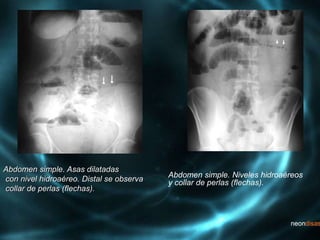

Abdomen simple. Asas dilatadas

con nivel hidroaéreo. Distal se observa

collar de perlas (flechas).

Abdomen simple. Niveles hidroaéreos

y collar de perlas (flechas).

Abdomen simple. Asasdilatadas con nivel hidroaéreo. Distal se observa collar de perlas (flechas). Abdomen simple. Niveles hidroaéreos y collar de perlas (flechas).